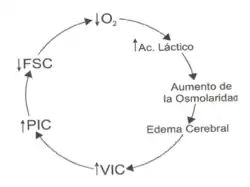

Alteraciones del flujo sanguíneo cerebral

El cerebro no puede almacenar sustratos y tiene una demanda alta de oxígeno por lo tanto requiere un aporte circulatorio continuo. Esta condición se deteriora en más del 50% de los pacientes dentro de las primeras 24 horas y suele mantenerse por 5 días. El flujo sanguíneo cerebral (FSC) en condiciones normales se satisface con el 15% del gasto cardíaco.[26] El FSC es relativamente constante a pesar del cambio en la presión arterial media (PAM). Es necesario que la presión de perfusión cerebral (PPC, equivalente a PAM-PIC) se mantenga por cercana de 60 mmHg. Si es menor, existirá isquemia y si es mayor, aumentará el volumen sanguíneo intracraneal.[27][5]

Alteraciones de la Presión intracraneal

Fisiológicamente, el SNC tiene una capacidad para amortiguar los cambios en la PIC (rango normal = 10mmHg ± 5mmHg) entre los que se incluyen la obliteración de las cisternas y ventrículos mediante la evacuación de líquido cefalorraquídeo (LCR) y la expulsión de hasta un 7% del volumen sanguíneo intracraneal fuera del lecho venoso cerebral.[28][29] Cuando la capacidad de regulación se agota, el paciente experimenta un aumento exponencial de su PIC (ver gráfico), lo cual ocurrirá de forma progresiva o de forma periódica. En este último caso habrá ascensos de 40-80 mmHg con una duración de 5 a 20 minutos. El aumento de la PIC reducirá la PPC por lo que inevitablemente se incrementará la isquemia cerebral preexistente y al no ser esta homogénea (por la compartamentalización de las meninges) la mayor magnitud de presión se localizará en las áreas donde exista una masa postraumática que se irá disipando mediante el desplazamiento del tejido cerebral llegando al enclavamiento.[5]